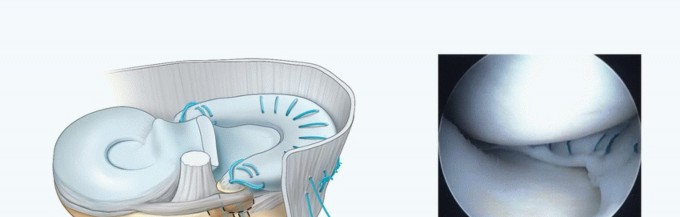

Via a shuttle suture, deliver the posterior bone plug suture through the notch and down the posterior tunnel, exiting anteriorly. Also, deliver the posterior passing suture through the arthrotomy and out of the posteromedial capsule to assist in passing the allograft. Via the parapatellar arthrotomy, deliver the meniscal allograft into the knee and fully seat the posterior bone plug into the posterior tunnel (

TECH FIG 6A-C

). A hemostat or probe can be used to aid in the delivery of the plug under the PCL. Applying a valgus stress to the knee while pulling on the posterior bone plug sutures through the tibial tunnel and the posterior passing suture helps to reduce the posterior horn. Similar to reducing a bucket-handle tear, a blunt trocar or probe may assist in reducing the meniscus under the femoral condyle (

TECH FIG 6D

).

Using zone-specific cannulas, secure the allograft to the periphery using an inside-out technique going from posterior to anterior (

TECH FIG 6E

). This will secure the posterior two-thirds of the graft to the capsule.

TECH FIG 6 • A,B. Medial meniscus delivery. Shuttle suture and delivery of the posterior bone plug and meniscus. C. Meniscus delivered into joint prior to reduction under condyle. D. Meniscus following reduction. E. Inside-out suture placement (posterior to anterior). F. Anterior recipient tunnel created by reaming over guide pin. G. Anterior bone plug seated into tunnel. H. Bone plug sutures tied over anterior bone bridge.

TECH FIG 6 •

(continued)

I. Schematic of bone plug and meniscus fixation. J. Arthroscopic view of final graft in position. 6. ## Medial Meniscus Transplant Combined with Revision Anterior Cruciate Ligament Reconstruction